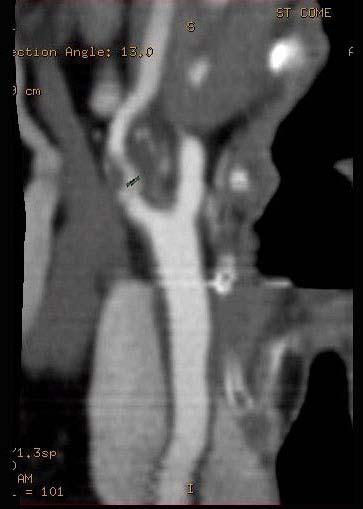

问题 65岁男性患者,近半年时常突发性头晕,行CT检查,三位重建图如下所示,选择正确的答案和描述 ( )

选项 A、考虑为颈内动脉粥样硬化性狭窄 B、考虑为颈外动脉粥样硬化 C、狭窄段可见低密度不强化血栓影 D、狭窄段管壁见点状致密钙化影 E、颈内动脉起始段有一长约3.0cm的狭窄段

答案 ACDE